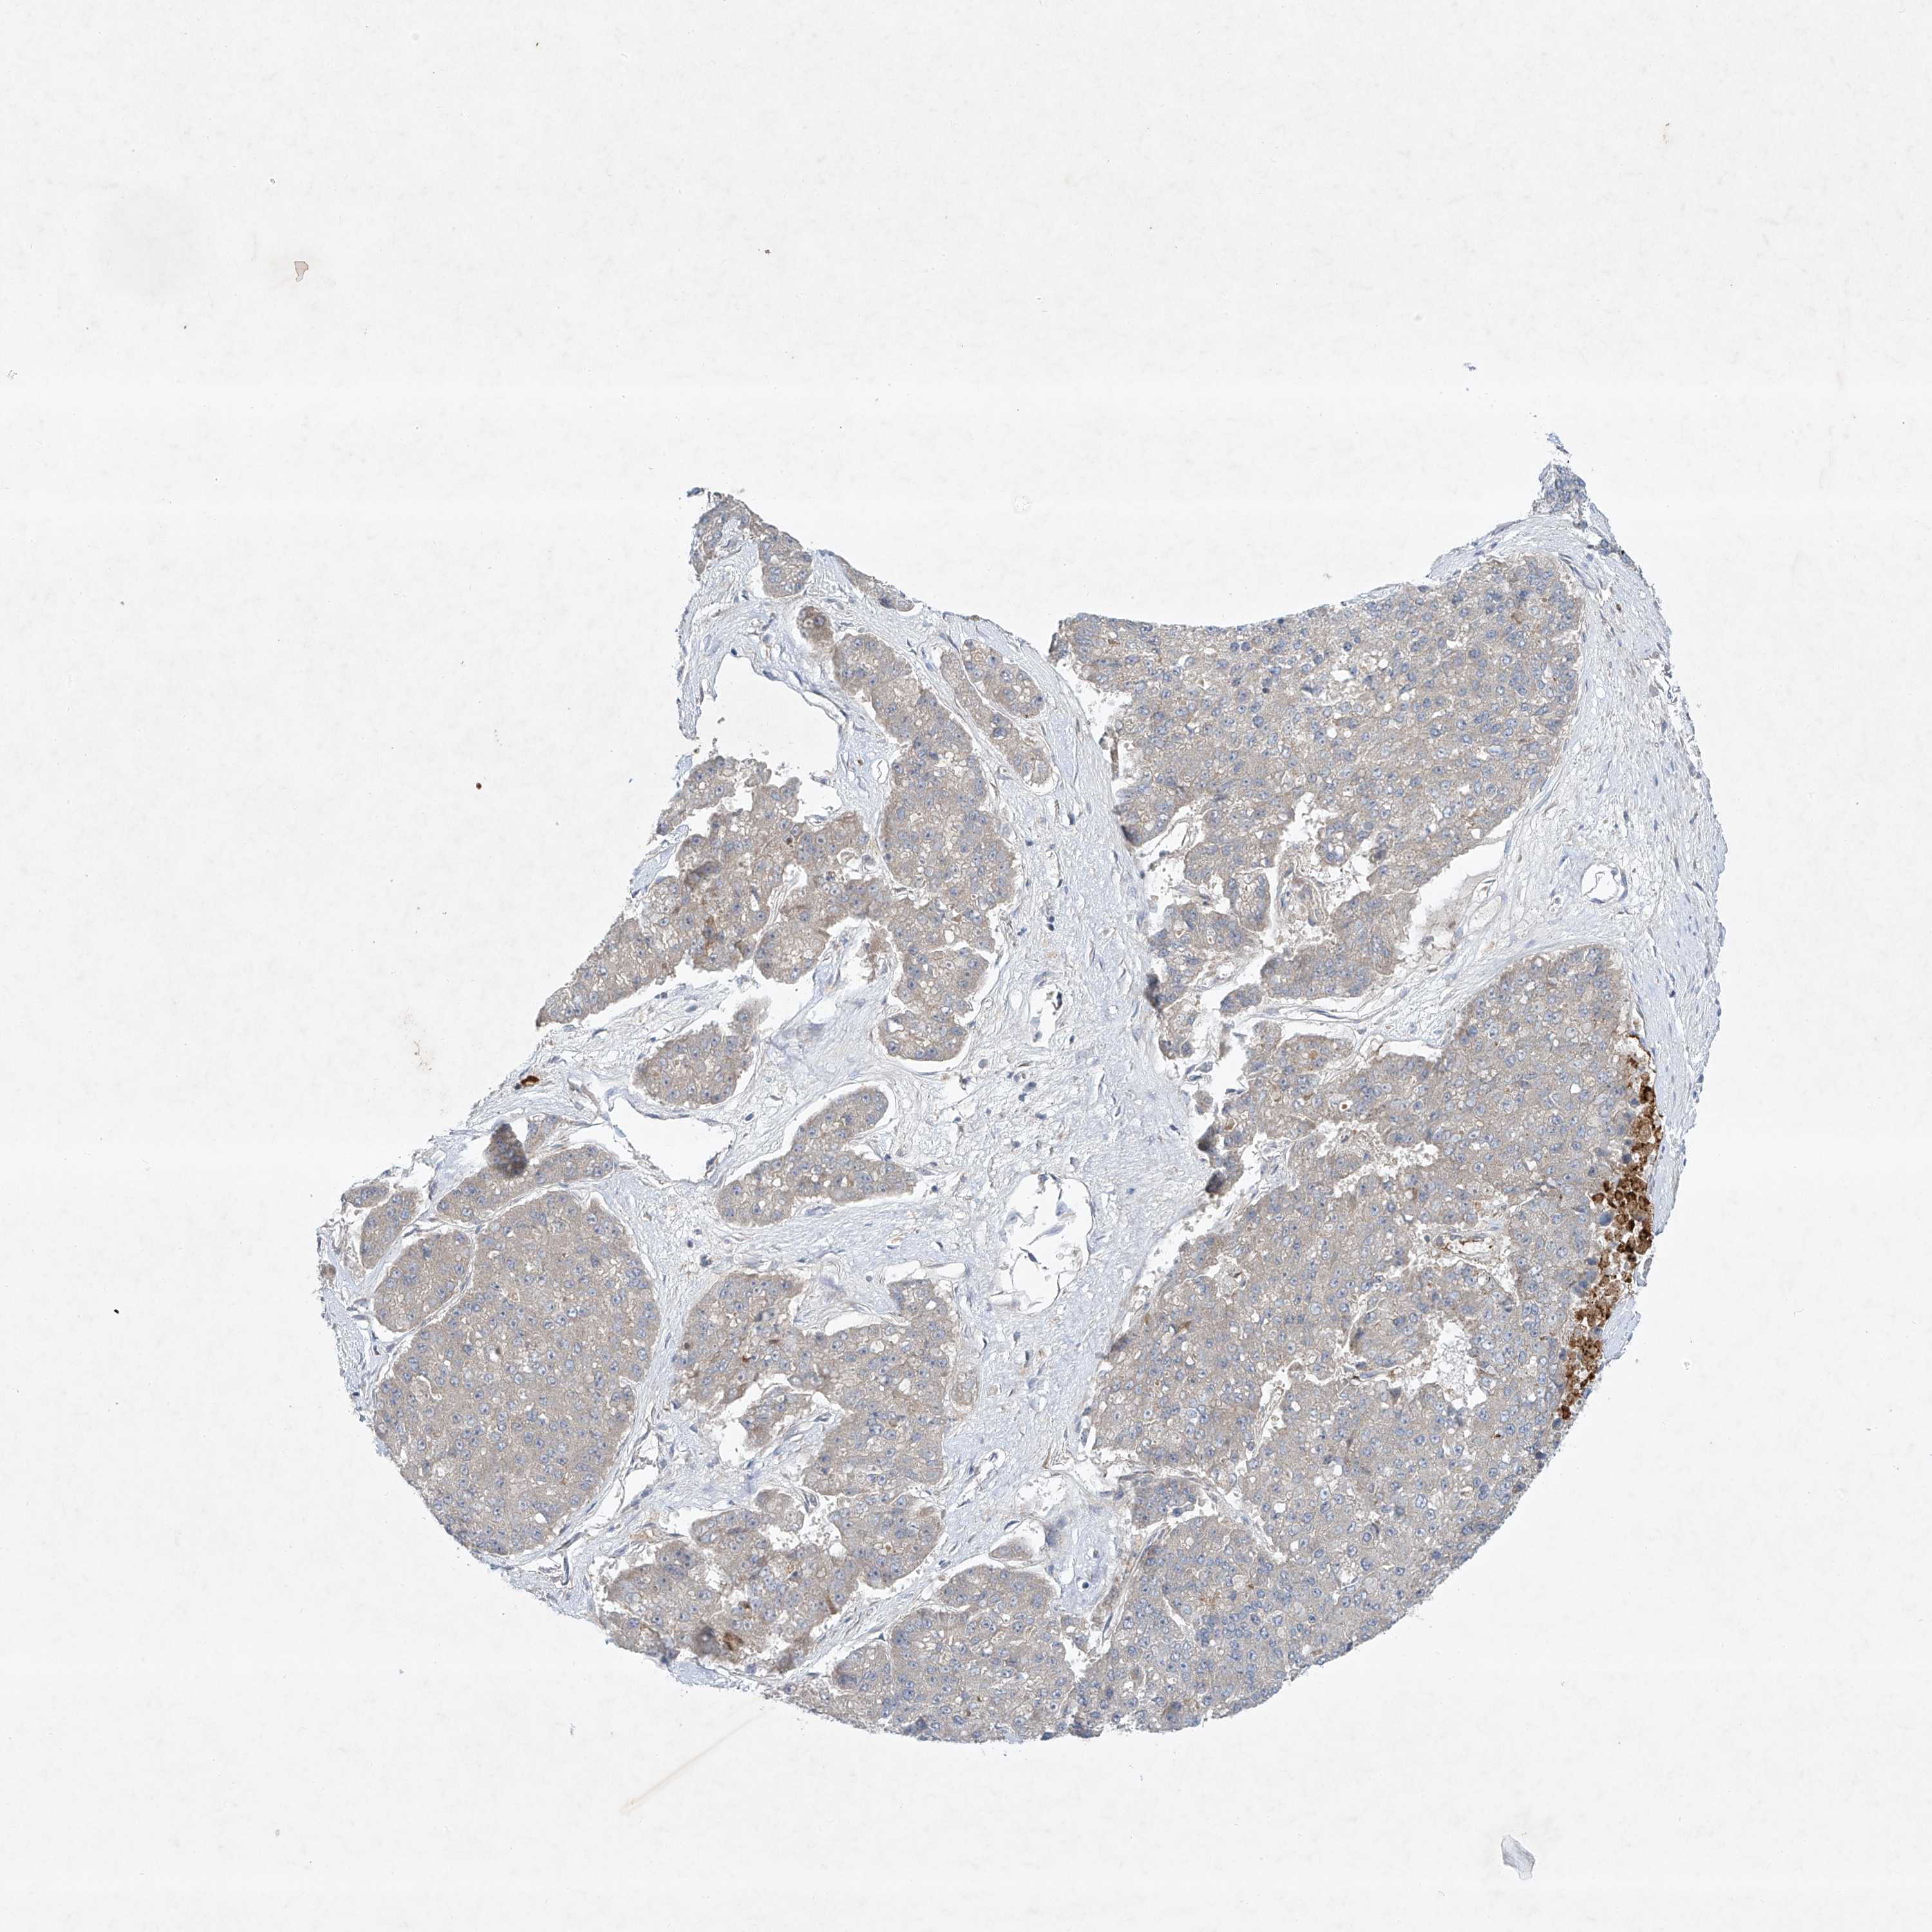

PANCREATIC CANCER - Protein expressioni

A mouse-over function shows sample information and annotation data. Click on an image to view it in a full screen mode. Samples can be filtered based on level of antibody staining by selecting one or several of the following categories: high, medium, low and not detected. The assay and annotation is described here.

Note that samples used for immunohistochemistry by the Human Protein Atlas do not correspond to samples in the TCGA dataset.

Antibody stainingi

Antibody staining in the annotated cell types in the current human tissue is reported as not detected, low, medium, or high, based on conventional immunohistochemistry profiling in selected tissues. This score is based on the combination of the staining intensity and fraction of stained cells.

Each image is clickable and will lead to virtual microscopy that enables deeper exploration of all samples and also displays staining intensity scores, fraction scores and subcellular localization as well as patient and tissue information for each sample.

Antibody HPA030164

Antibody HPA030165

Antibody HPA030166

Staining

High

Medium

Low

Not detected

Intensity

Strong

Moderate

Weak

Negative

Quantity

>75%

75%-25%

<25%

None

Location

Nuclear

Cytoplasmic/membranous

Cytoplasmic/membranous,nuclear

Adenocarcinoma, NOS